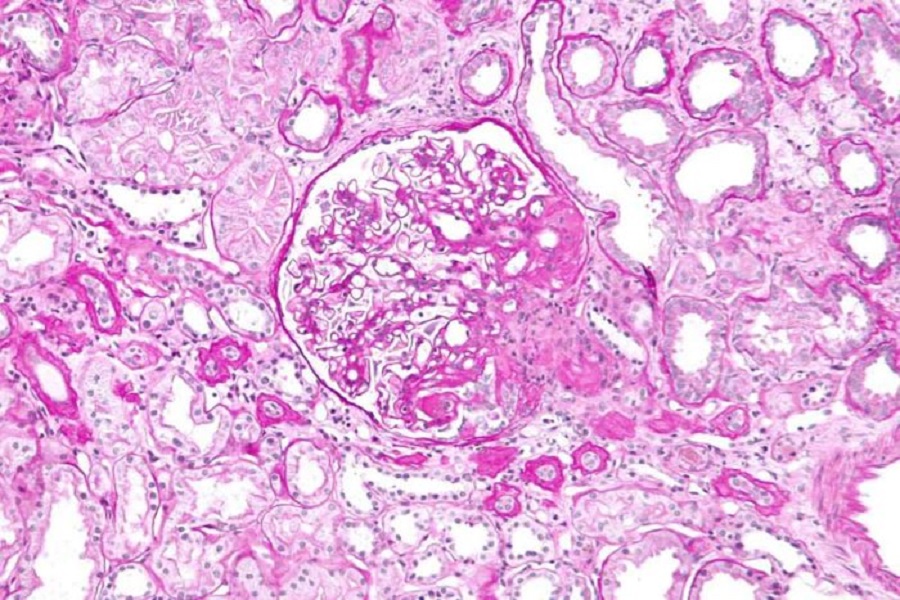

Using a more sensitive test than is commonly used in the NHS, researchers have been able to show, for the first time, that even mild kidney disease is associated with an increased risk of developing and dying from cancer.

The new research, led by the University of Glasgow and published in the journal EClinicalMedicine, shows that the more sensitive cystatin C test was able to identify a heightened risk of developing and dying from cancer in people with chronic kidney disease.

Chronic kidney disease, characterised by gradual loss of kidney function over time, is common, affecting around 10% of the population. Cancer is already known to be more common in people with kidney failure, especially in people requiring dialysis or a kidney transplant. Although kidney failure is relatively uncommon, mild kidney disease may be present in a third of the population, although it is usually asymptomatic, not routinely diagnosed and therefore monitored infrequently.